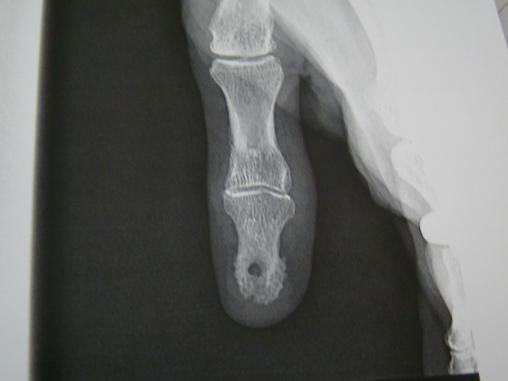

Coll P. Frances La radiographie montre une ostéolyse importante due à la compression exercée par la kérato-acanthome